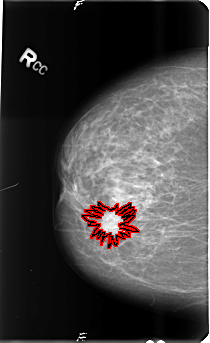

B_3488_1.RIGHT_CC

RIGHT_CC LINES 4792 PIXELS_PER_LINE 2936 BITS_PER_PIXEL 12 RESOLUTION 50 OVERLAY

FILE: B_3488_1.RIGHT_CC.OVERLAY

TOTAL_ABNORMALITIES 1

ABNORMALITY 1

LESION_TYPE MASS SHAPE IRREGULAR-ARCHITECTURAL_DISTORTION MARGINS SPICULATED

ASSESSMENT 5

SUBTLETY 5

PATHOLOGY BENIGN

TOTAL_OUTLINES 1

BOUNDARY